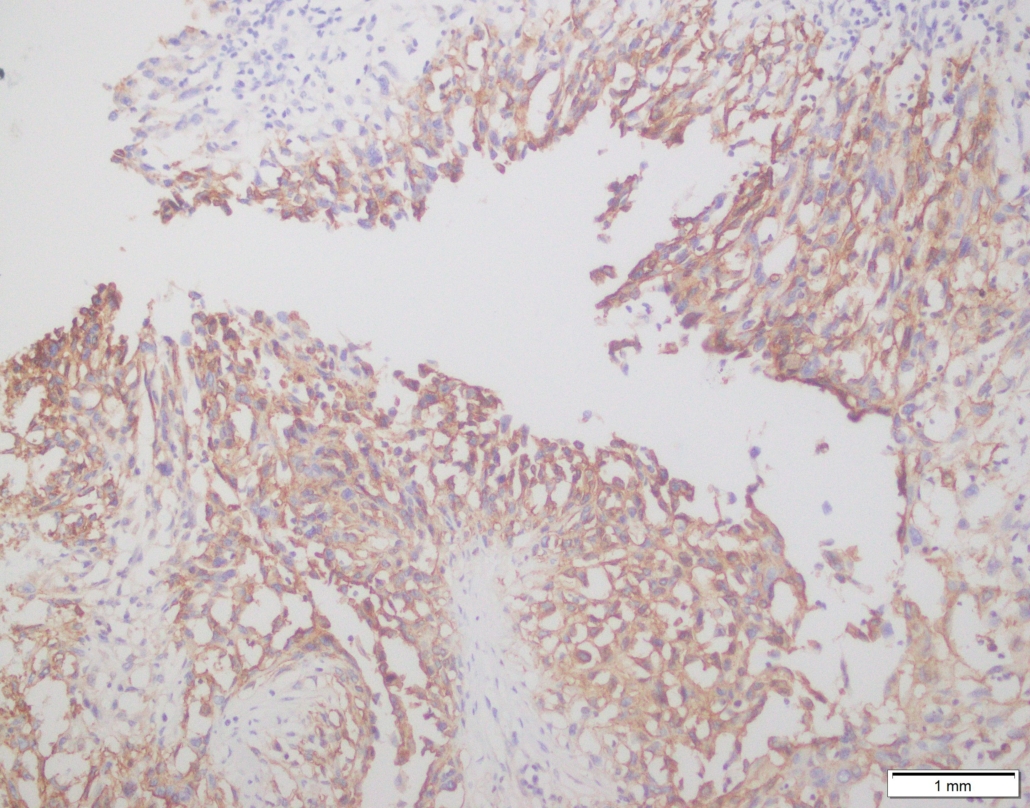

Case 03

Case presented by Dr Shaarif Bashir, FCPS (PAK), Shaukat Khanum Memorial Cancer Hospital and Reserach Centre, Pakistan